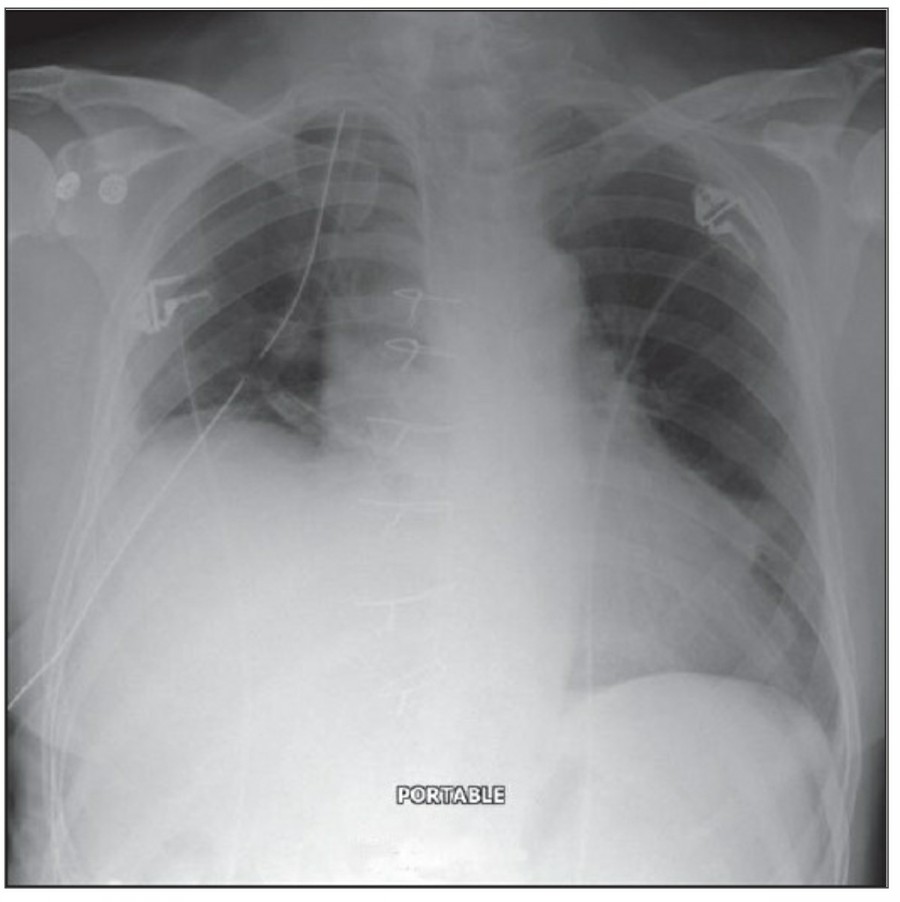

Thoracotomy를 시행받고 나온 환자의 initial postoperative chest X ray에서 각종 line과 endotracheal tube, thoracotomy tube, mediastinal drains, central venous catheter 등을 확인할 수 있을 것이다. 이러한 device들은 그 위치가 제대로 있는지 확인해야 한다.

CABG를 받은 환자에서 lower lobe atelectasis는 흔한데, 주로 왼쪽에 잘 나타나며 수일 내에 별다른 합병증 없이 회복된다. mediastinum도 약간 확대되어 보일 수 있는데, 만약 그 diameter가 많이 증가한다면 mediastinal hemorrhage 등을 시사할 수 있다. CABG 시행 후 약간의 좌측 pleural effusion은 있을 수 있지만 그 양이 많거나 증가한다면 respiratory compromise를 줄이기 위해 intervention이 필요할 수 있다. 따라서 이전의 사진과 비교를 해서 pleural effusion 양의 변화가 있는지 확인이 필요하겠다.